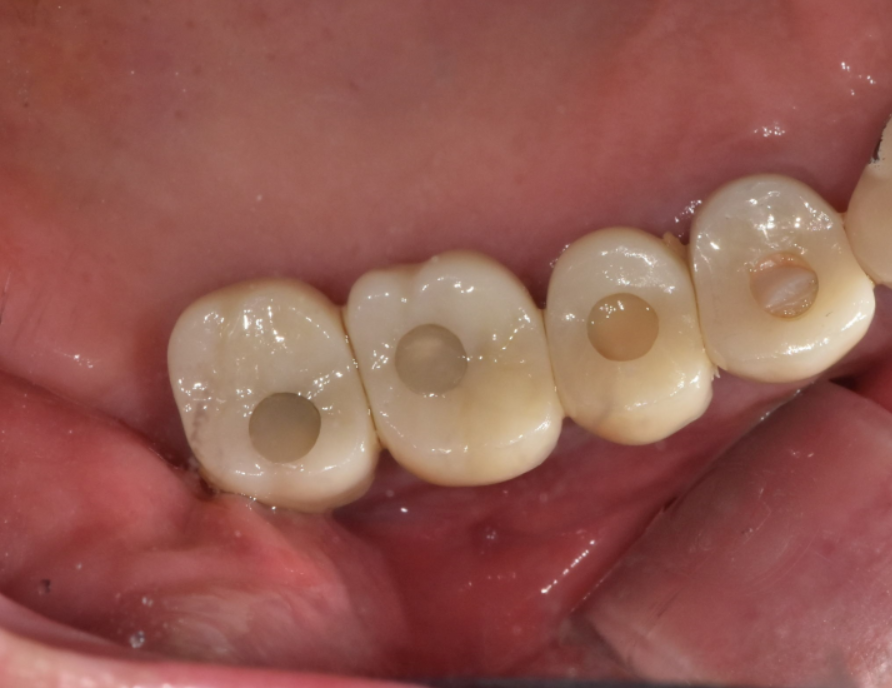

24.01.22

고덕동 치과치료 트렌드 따라 가야겠죠?

예전에는 은니로 많이 치료했지만

하얗고 단단한 지르코니아로~!

색깔도 맞춰서 마무리 해드렸습니다.